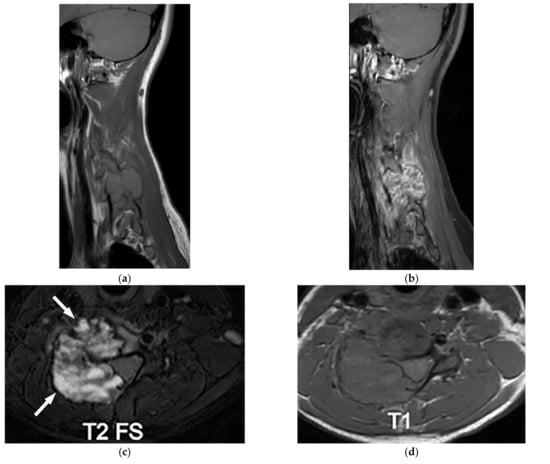

Figure 8.

A 24-year-old man with multiple bone lesions. (A) The axial non-contrast CT in bone window demonstrates expansile lytic bone lesion with intact cortex within the spinous process of thoracic vertebrae (arrow); no periosteal reaction, cortical disruption, or soft tissue mass was found. (B) Sagittal T1W image shows expansile bone lesions with hyposignal intensity and intact cortex within the spinous process of multiple cervical spines (arrow). (C) Frontal image of pelvis shows bilateral expansile lytic bone lesions with bubbly appearance and typical shepherd’s crook deformity in the left side.